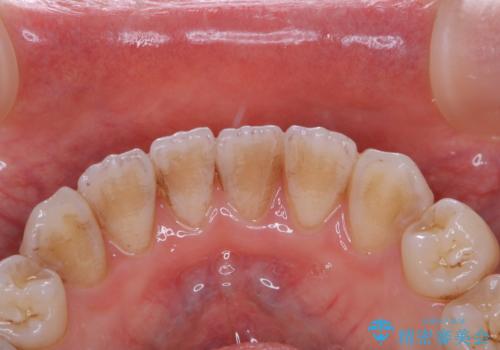

- インビザラインでの矯正治療中の方です。全体的に黄ばみ・黒ずみが気になるとのことでした。

PMTC(保険外治療)は、毎日の歯磨きで落としきれない汚れや、コーヒ、紅茶・タバコのヤニなどの着色も除去します。目には見えない歯と歯の間・歯肉の境目・インビザライン中はアタッチメント周囲などに残っているプラーク(歯垢)もしっかり取り除きます。PMTCでは専門的な機械や材料を使用して、徹底的に汚れを除去するため、虫歯・歯周病・口臭予防などにつながります。